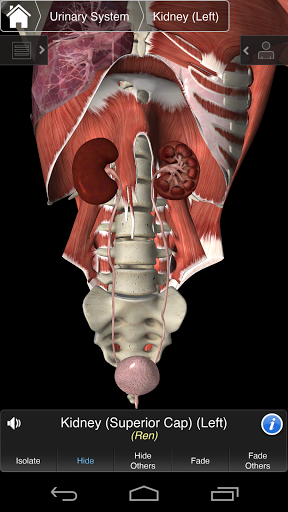

⁃Urinario

Essential Anatomy 3 es receptivo, visualmente impactante y sin esfuerzo. La aplicación es totalmente en 3D, lo que significa que puedes ver cualquier estructura anatómica de forma aislada y desde cualquier ángulo.

Essential Anatomy 3 está diseñado pensando en el usuario: el cuerpo mismo se convierte en la interfaz. A diferencia de otras aplicaciones 3D, que se basan en arreglos anatómicos predefinidos y disecciones regionales para guiar al usuario, Essential Anatomy 3 de 3D4Medical le permite encontrar lo que está buscando sin complicaciones.

---- Más de 4,000 estructuras anatómicas altamente detalladas

---- Modo de selección múltiple - Ocultar / Fundir / Aislar estructuras individuales o múltiples

---- Corregir la pronunciación de audio para cada estructura

---- Nomenclatura latina para cada estructura anatómica